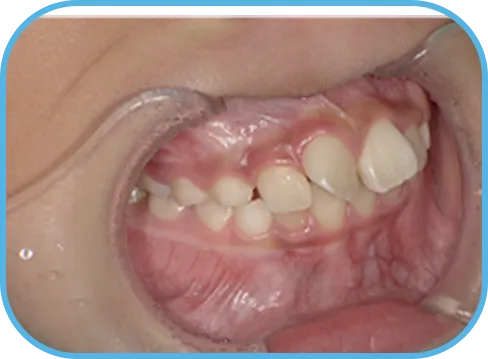

治療前右側からの歯の様子

• 左 側

治療前左側からの歯の様子

主 訴

前歯がでている、噛み合わせが深い

治療内容

インビザライン・ファースト

治療期間

10か月

治療費(税別)

450,000円+診断料30,000円

リスク・副作用

• 親知らずの影響や加齢などによって、凸凹が生じる可能性があります。

• 治療の初期段階では痛みや不快感が生じやすくなりますが、1週間前後で慣れます。

• 顎の成長発育によって、噛み合わせや歯並びが変化する可能性があります。

• 状況により当初予定した治療計画を変更する可能性があります。